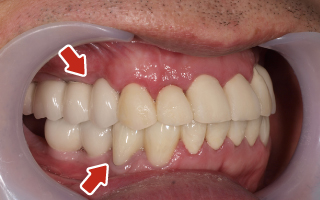

Before

After

| 68歳 男性 | 紹介 |

|---|---|

| 主訴 | れ歯が合わない 食べにくい 人生を豊かにしたい |

| 処置内容 |

上顎4本で12歯(オールオン4)、下顎4本5歯 上下抜歯即時埋入、即時荷重(手術当日にインプラントの上に仮歯装着) |

| 治療費用 | 上顎: 約220万(税込) 下顎: 約180万円(税込) |

| 治療期間 | 上顎: 9ヶ月 下顎: 6ヶ月 |

| リスク |

術後の腫れ、痛み(ピークは3日後、1週間で軽減) 上部構造物、仮歯の破折、人工歯根脱落リスクがあります |